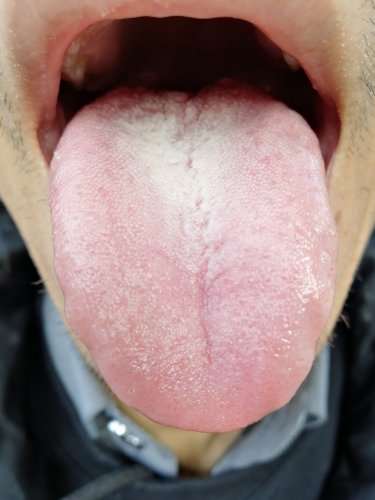

你好,27楼的内容就是我目前的症状。再加上肩膀和背僵硬,肋骨有时候会不舒服现在具体什么症状??

做腹部按摩的时候,肚脐左上方,靠近肋骨下有一点特别痛

给大家反馈下,3付吃了5天后的感受。薏米50克茯苓20白术15猪苓15桂枝35干姜20当归50克红枣12枚黄芪30克灸甘草20熟地山药山萸肉枸杞各30克杜仲30克玉竹10克独活15,人参25 。1.睡眠前几天明显改善、但是昨天晚上又失眠了,感觉脑袋发热,静不下来。2.有2次遗精。3.嘴里清水明显减少。偶尔腰酸加重。

你这个病不需要补,本来其实就是有湿热,脾胃消化又差,再用这种干姜黄芪熟地,确实容易加剧郁热产生遗精。给大家反馈下,3付吃了5天后的感受。薏米50克茯苓20白术15猪苓15桂枝35干姜20当归50克红枣12枚黄芪30克灸甘草20熟地山药山萸肉枸杞各30克杜仲30克玉竹10克独活15,人参25 。1.睡眠前几天明显改善、但是昨天晚上又失眠了,感觉脑袋发热,静不下来。2.有2次遗精。3.嘴里清水明显减少。偶尔腰酸加重。

用清热化湿的办法应该能缓解,如果脾胃受不了清热,就用宣通化湿的办法

枳壳白芍用起来也要注意,你的脾虚,这种药用下去马上大便就变细